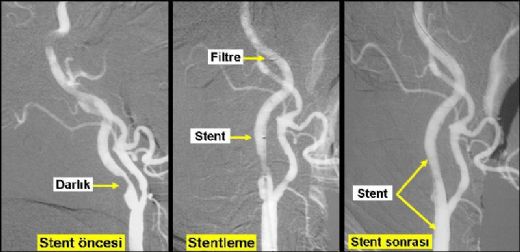

Bu nedenler, kılcal damarların yapısını zayıflatarak kanama riskini artırabilir. Tedavi Yöntemleri Kılcal damar kanaması tedavisi, kanamanın nedenine ve ciddiyetine bağlı olarak değişkenlik göstermektedir. Genel olarak uygulanan tedavi yöntemleri şunlardır: